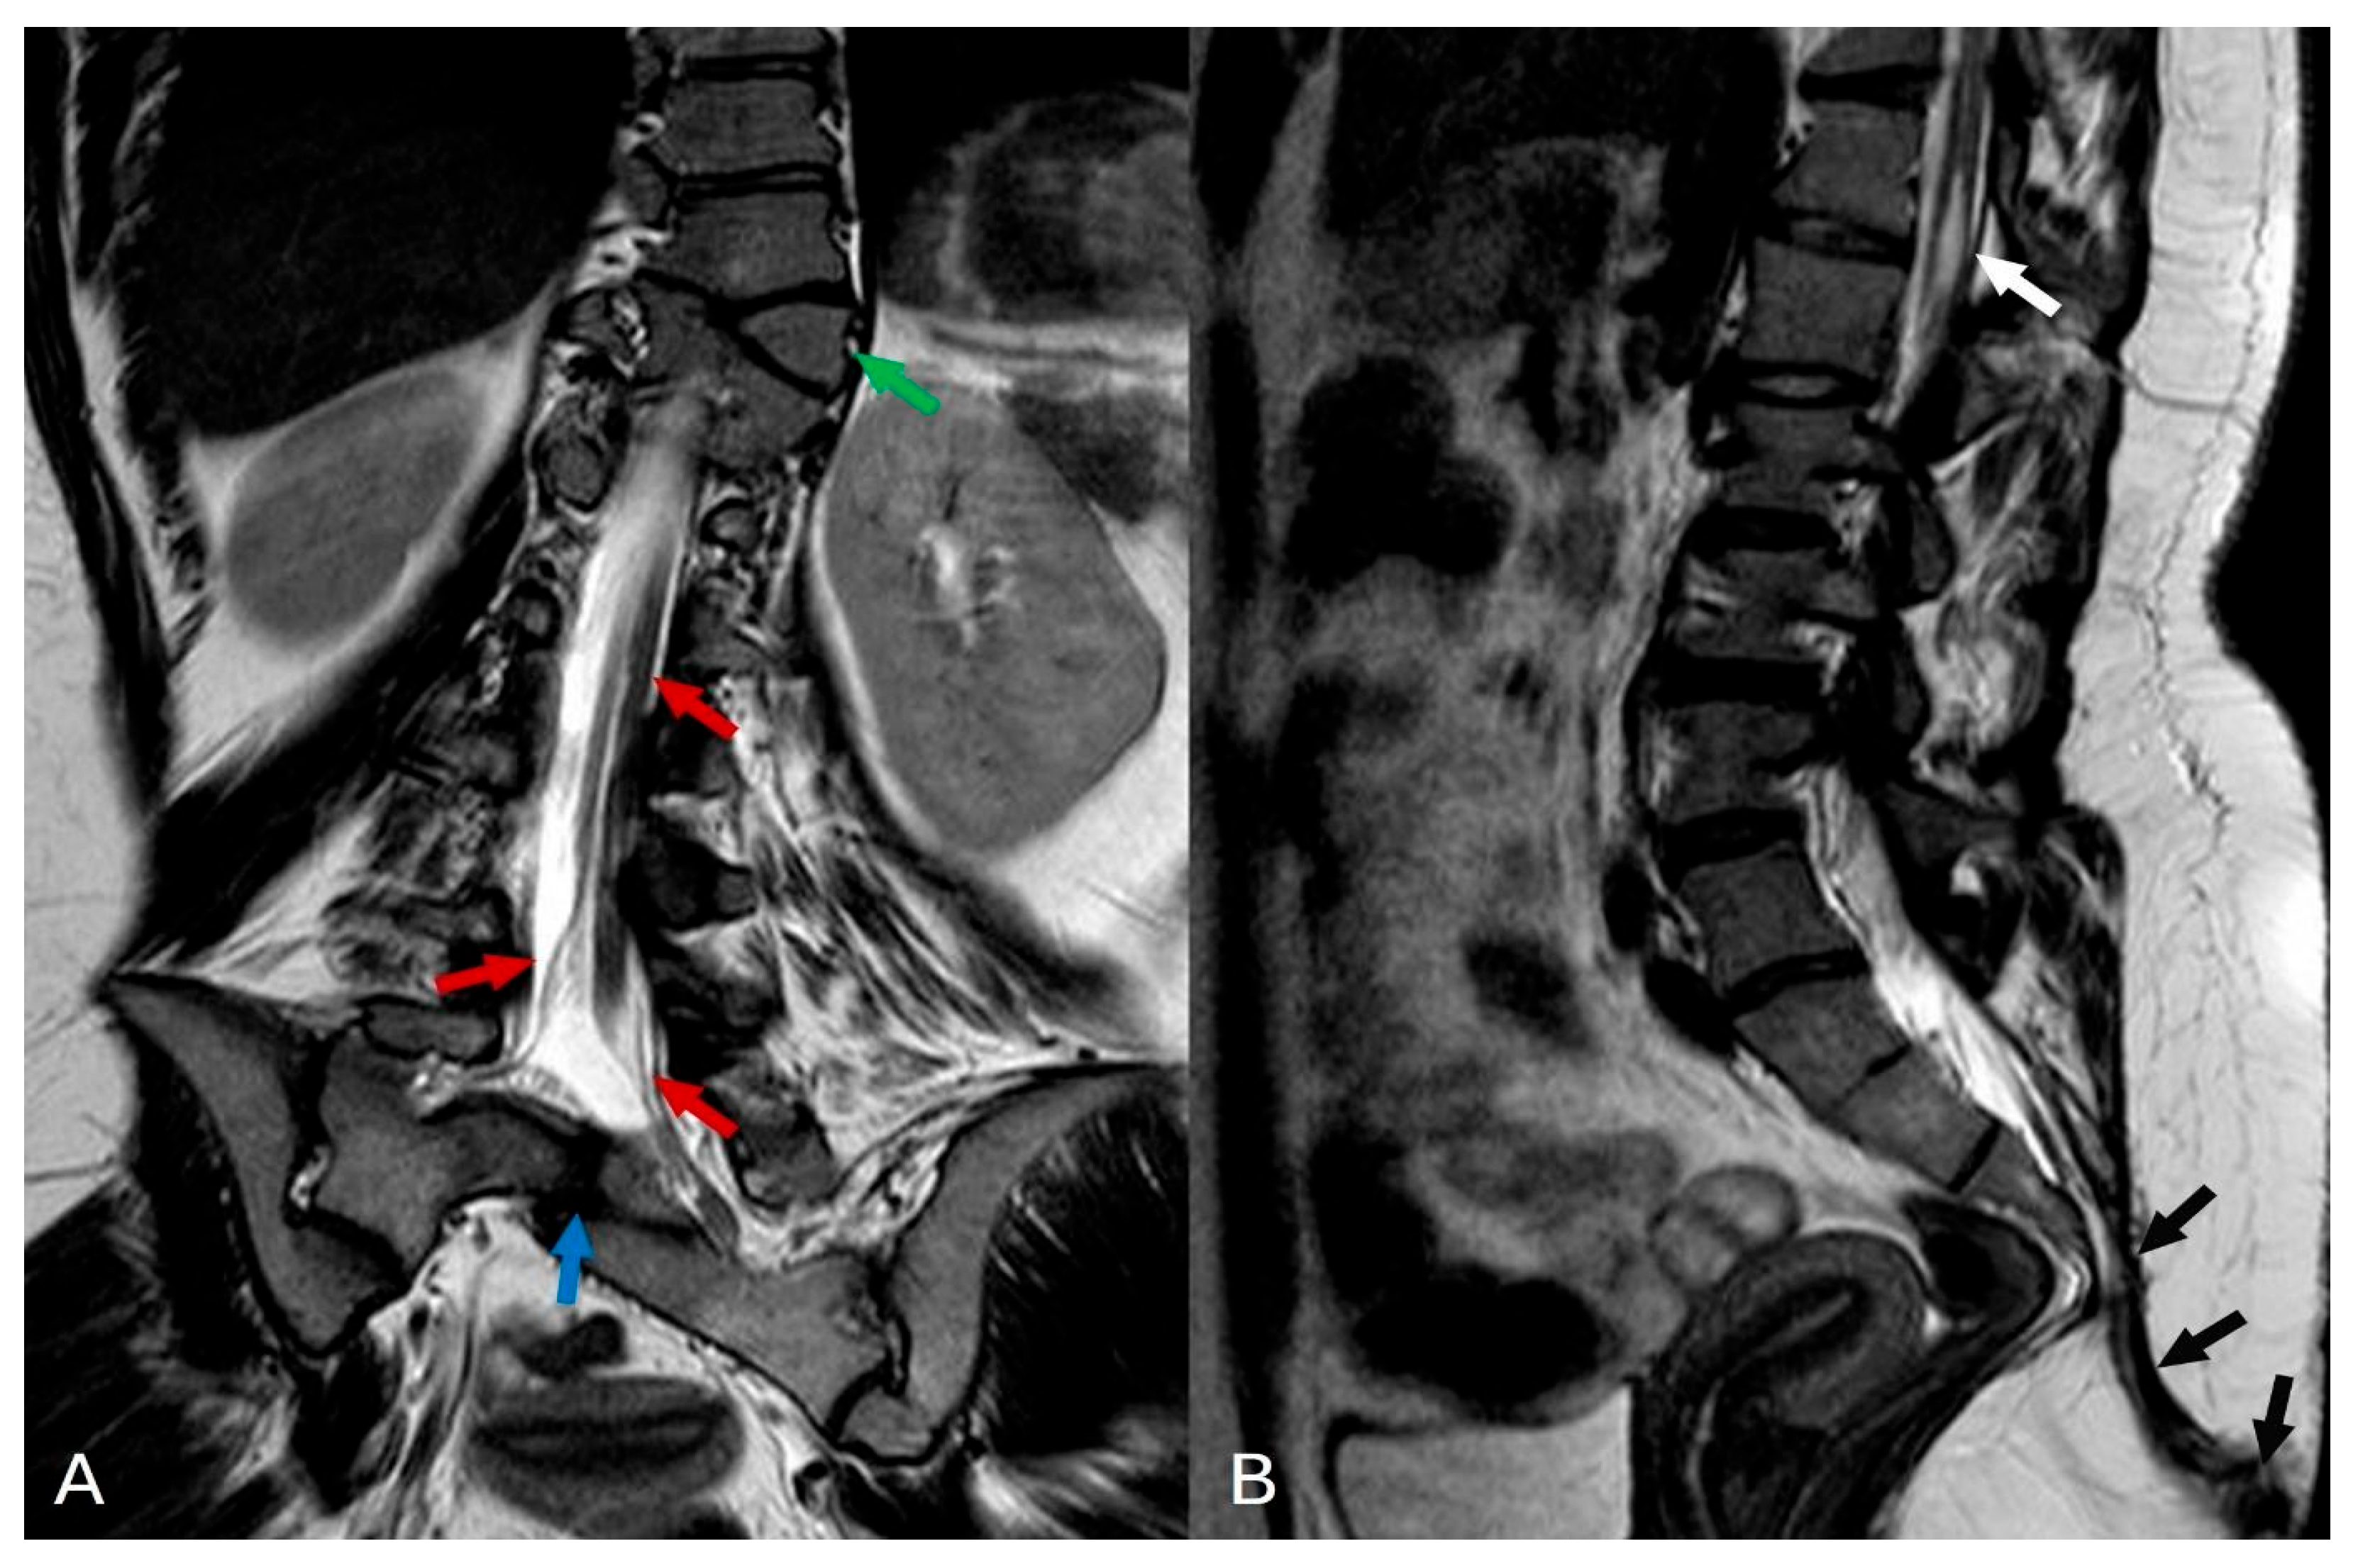

Figure 3.

(A) In the T2-weighted turbo spin echo (TSE) coronal plane, several significant findings are noted: butterfly deformity in Th11 with right side of vertebrae fused to Th12 (green arrow), a split spinal cord with a single thecal sac indicative of diastematomyelia type II (red arrows), and partial segmentation of the sacral vertebrae (blue arrow). (B) In the T2 TSE sagittal plane, notable findings include a small syringohydromyelia (white arrow) observed at the thoracolumbar junction (Th12-L1 level), as well as the presence of a sinus pilonidal fistula (black arrows).